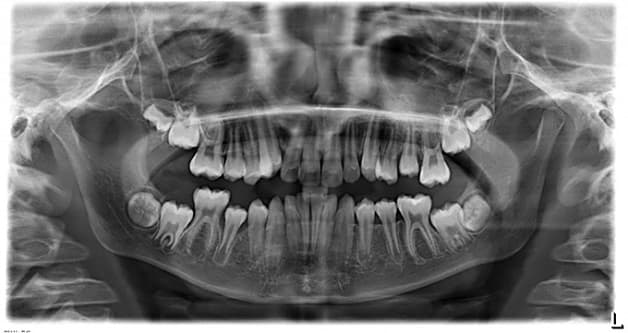

3.3. Chụp X quang răng: Panorama

Bác sĩ sẽ chỉ định thực hiện chụp Panorama hay chụp toàn cảnh răng khi cần kiểm tra toàn bộ khoang miệng. Phương pháp này cho ra hình ảnh chụp sắc nét và độ phân giải cao.

Chụp X quang toàn răng được thực hiện theo các bước:

B1: Một số trường hợp người khám sẽ được yêu cầu mặc áo chì bảo vệ.

B2: Sau khi đã được mặc trang phục chuyên dụng, người khám sẽ đứng trước máy chụp X quang, cắn vào một tấm nhựa được gắn vào máy và đứng yên trong thời gian chụp.

B3: Nhân viên y tế sẽ thực hiện điều chỉnh và cho máy chụp hoạt động.

B4: Máy chụp X quang sẽ di chuyển quanh một vòng xương hàm của người khám trong khoảng 12 – 15 giây.

B5: Người khám sẽ nhận được phim chụp và bác sĩ sẽ thực hiện đọc kết quả.

Ưu điểm của phương pháp chẩn đoán hình ảnh răng này chính là có thể nhìn thấy 2 hàm trên và dưới trong cùng 1 phim, hình ảnh có độ phân giải cao và phù hợp với mọi đối tượng. Ngoài ra, Chụp toàn cảnh răng có thể phát hiện và chẩn đoán nhiều bệnh lý răng miệng khác nhau như răng mọc lệch, áp xe, tổn thương xương hàm,…

Chụp X quang răng cho phép bác sĩ đánh giá được cả hàm trên và hàm dưới trên cùng 1 phim chụp